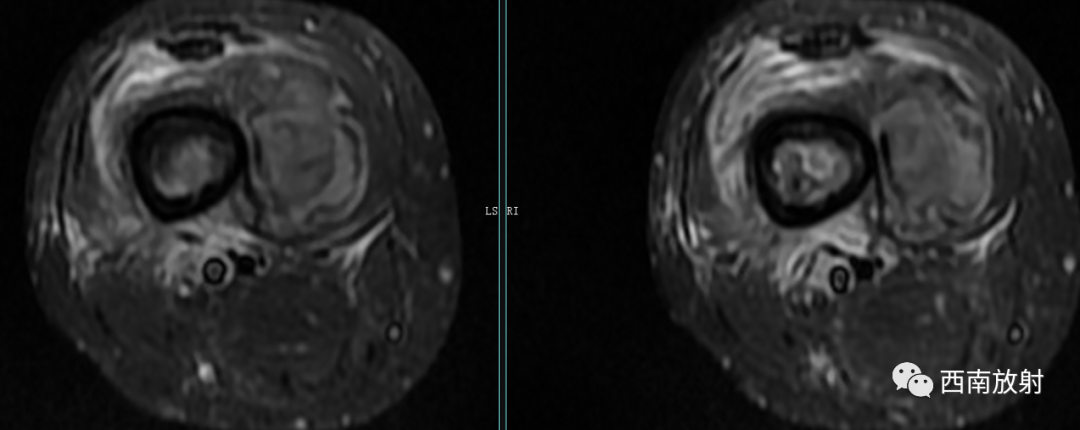

CT显示骨破坏、脓肿、死骨及骨膜增生、骨质增生硬化,呈骨小梁密度增高、模糊,髓腔密度增大、狭窄,皮质增厚。MRI显示早期骨髓内广泛分布的斑片异常信号,与邻近正常骨髓信号相比较,T1WI信号减低,T2WI信号增高,脂肪抑制T2WI 或STIR 等序列上病变显示更清楚,骨皮质周围软组织内呈弥漫分布的T1WI低信号及T2WI高信号影,边界模糊。出现骨膜反应,骨皮质不规则破坏,脓肿及死骨形成。

关于脂肪征

▲MRI脂肪征:病灶内单发或多发,T1WI上呈高信号,脂肪抑制序列信号明显减低。急性骨髓炎的脂肪球征发生机制:骨髓炎的炎性反应致骨髓腔内充血、渗出及水肿最终导致髓内压力增高,髓腔内大量脂肪细胞(即髓脂细胞)快速坏死释放出游离脂质并聚集形成脂肪球[2-3]。